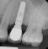

Poza Implant dentar

1. Implantologie ( implanturi dentare )